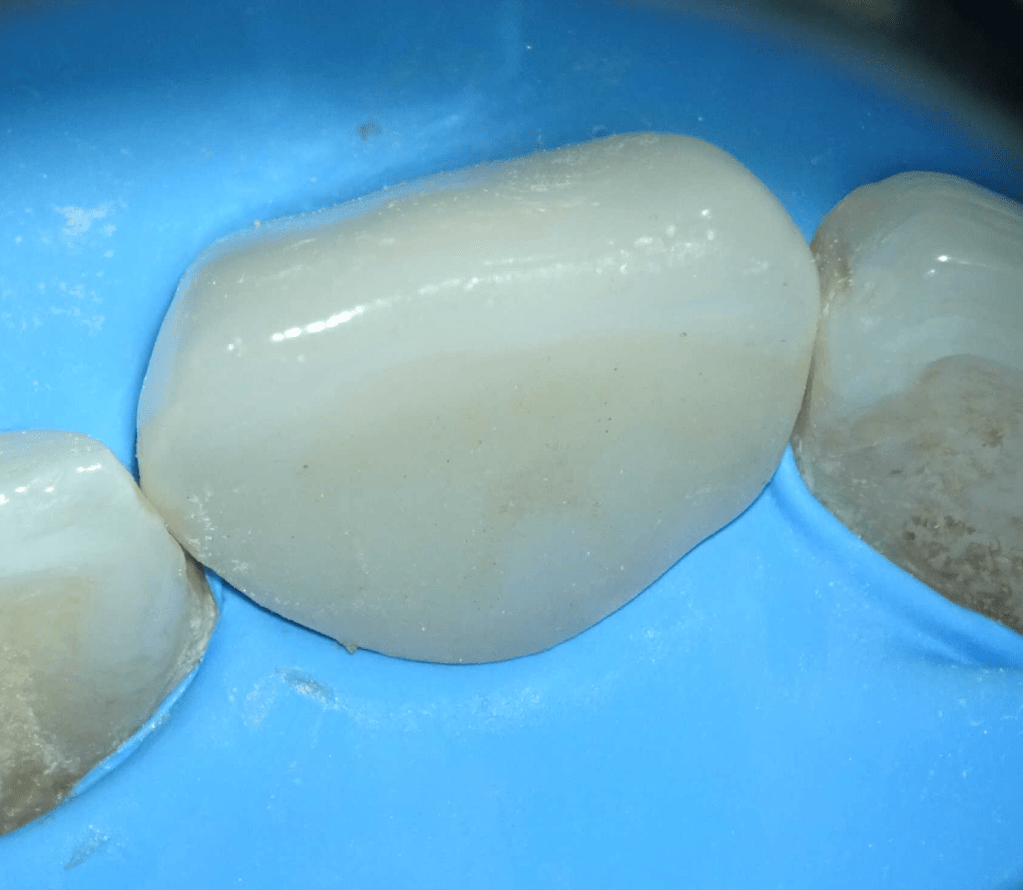

Acceso ultraconservador a través de incrustación reciente

Reconstrucción preendodóntica

Reco preendo + 4 conductos molar superior

Reco preendo, 2o Molar superior